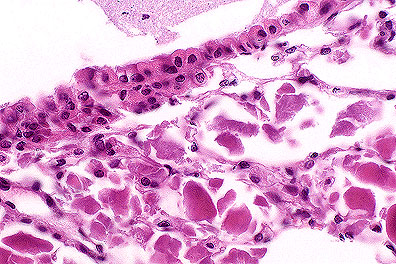

Marked tubular epithelial swelling due to glycogen accumulation in a knockout mouse (HE, 400X, 85K)

Gross Pathology: Liver enlarged. Kidneys pale and enlarged.

Contributor's Diagnosis and Comments: Glycogen storage disease, liver and kidney. Glucose-6-phosphatase knockout mouse.

AFIP Diagnosis: 1. Kidney, tubular epithelium: Vacuolar change (glycogenosis), diffuse, severe, 129 x C57BL strain mouse, rodent.

2. Liver: Vacuolar change (glycogenosis), diffuse, severe, with multifocal necrosis, extramedullary hematopoiesis, and biliary hyperplasia.

Conference Note: Glycogen storage diseases result from genetically inherited deficiencies in enzymes required for glycogen synthesis or catabolism. In man, 12 types of glycogen storage diseases have been identified based on the enzyme that is deficient. Although a slightly different clinical picture is present for each type of glycogen storage disease, they can be placed into three categories depending upon the organ system(s) most affected (hepatic, myopathic, or systemic).

Type I (von Gierke's disease) glycogen storage disease results from the deficiency of glucose-6-phosphatase. In humans, this deficiency results in hepatomegaly and renomegaly, both caused by intracytoplasmic accumulations of glycogen and lipid. People affected with von Gierke's disease also have hypoglycemia and hyperlipidemia due to deranged glucose metabolism. The hyperlipidemia predisposes those afflicted with type I glycogenosis to the formation of xanthomas and abnormal fat deposits. Type I glycogenosis has been induced in mice by X-radiation, and now by the development of the gene knockout mouse as in the submitted case. This knockout mouse develops a clinical syndrome very similar to that of human type I glycogenosis and may serve as an animal model for that disease.